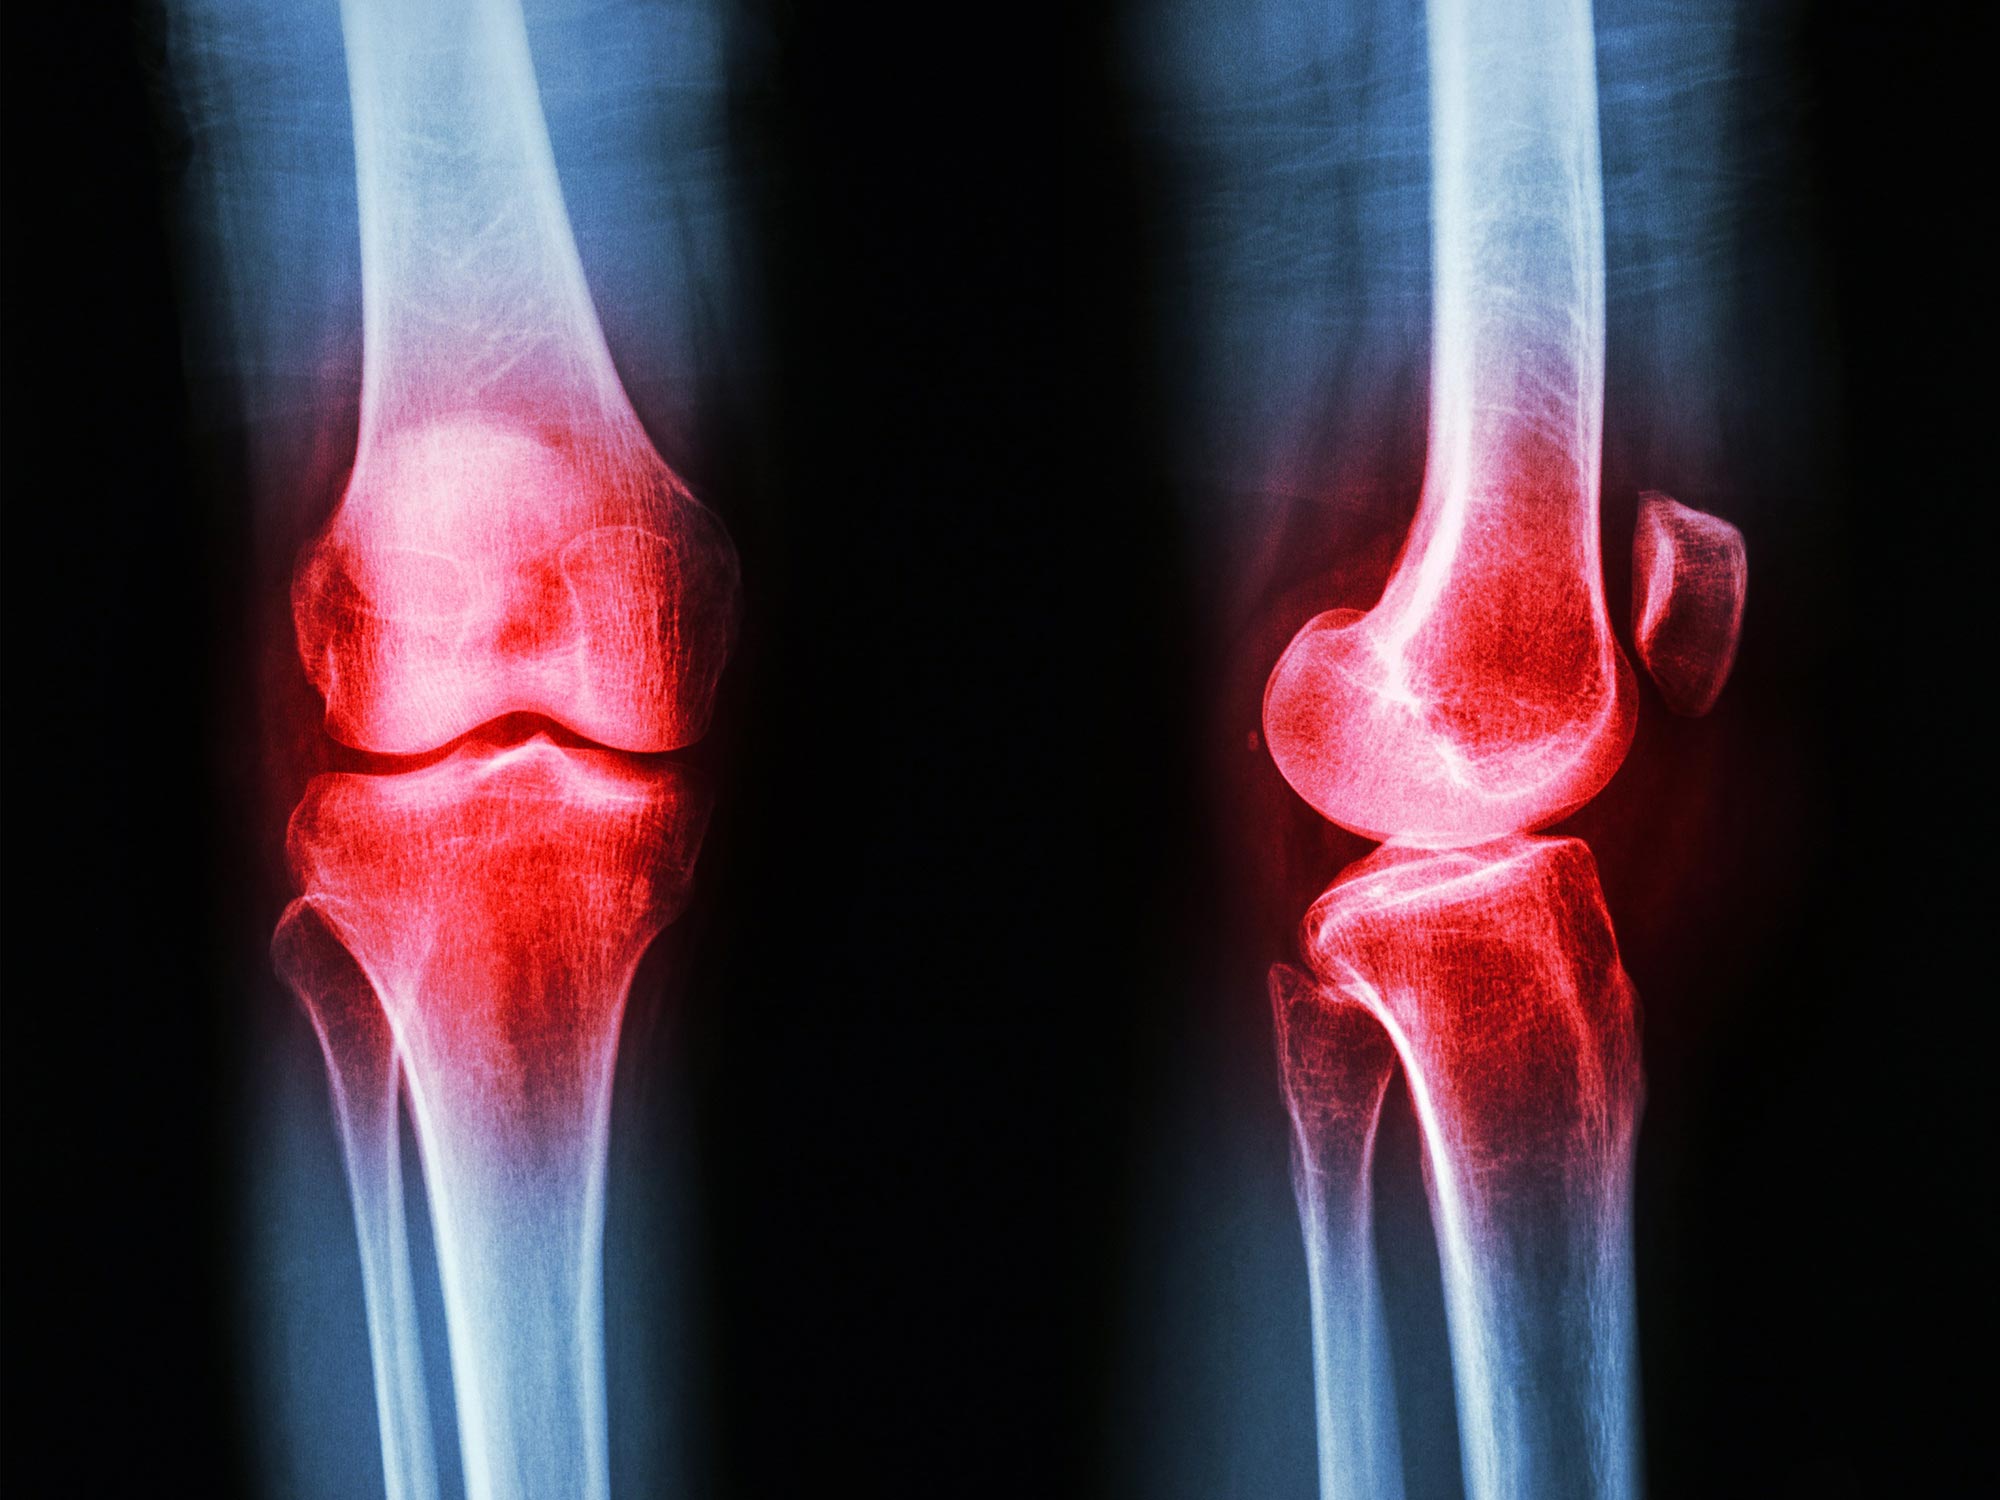

GLP-1, or glucagon-like peptide-1, is a hormone produced in the gut that plays crucial roles in regulating insulin and blood sugar. It has garnered attention primarily for its role in diabetes management and obesity treatment. But what if I told you this same hormone has a potential role in the joints? It’s as if we’ve taken a magnifying glass to a well-worn map and discovered a hidden path. Researchers at Aarhus University’s Department of Biomedicine have found GLP-1 lurking in the joint fluid of arthritis patients, prompting questions about its potential.

Current medical treatment for arthritis usually revolves around controlling inflammation and alleviating pain rather than addressing the root causes of the disease. But with GLP-1 making an appearance in joint fluids, there’s an opportunity to rethink our approach. Researchers observed that although GLP-1 exists in small amounts in the joints, the dosage delivered through GLP-1-based medications is substantially higher than what the body naturally produces.

What did they find? A surprising correlation: the levels of GLP-1 in joint fluid closely mirrored those found in the bloodstream. It was almost poetic — a reminder that what flows through our veins and nourishes our bodies also influences even the most complex systems, like our joints. This new understanding provides a scientific backdrop against which we can paint a future filled with possibilities.